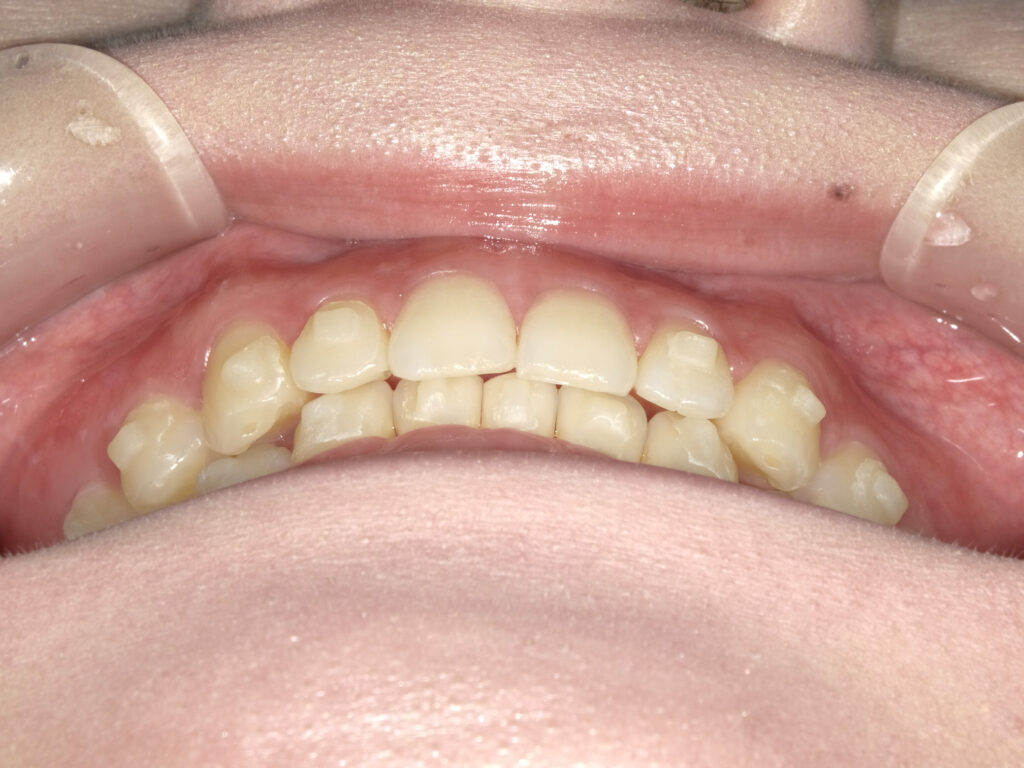

正面

治療前